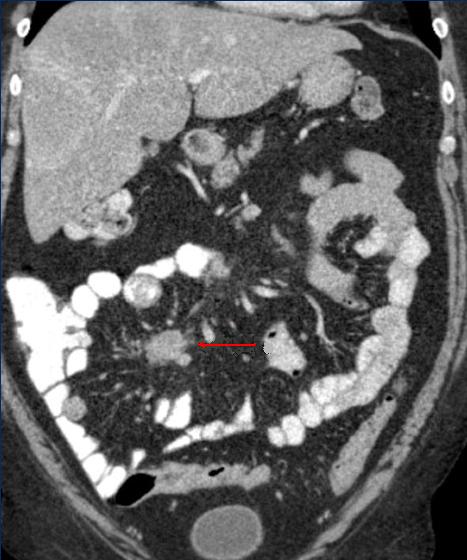

Masse fibrose par

desmoplastique meseterique en forme de

image spiculaire ( fleche rouge ) d'une tumeur

carcinoide de l'intestin . Image TDM en coupe

coronal |

Image d'une masse

fibreuse desmoplastique retractile mesenterique (

fleche jaune ) avec des nodules de calcifies.

Image de tumeur

multicentrique avec masse a hyper -dense nonhomogene

spidiculee mesenterique et calcifiee . Tumeur

carcinoide .( Image TDM en coupe coronal ) |